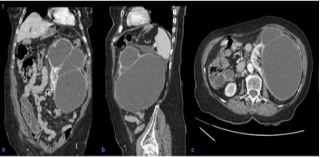

An 80-year-old woman with a history of metabolic syndrome, ischemic heart and cerebrovascular disease was admitted at the emergency department with asthenia and left abdominal and flank pain. She was on day 5th of empiric cefuroxime for urinary tract infection. On physical examination, the patient was febrile, but hemodynamically stable; an abdominal mass in the left flank was evident and painful on deep palpation; ipsilateral Murphy’s sign was present. Laboratory studies showed a marked elevation of C-reactive protein (329.9 mg/L), normal renal function, and mild isolated leukocyturia (70/μL) on urinalysis. A contrast-enhanced abdominal-pelvic computed tomography scan revealed an enlarged left kidney conditioned by a multiloculated cystic lesion (14 X 11 mm in the axial plane; 21 mm in the longitudinal plane), with homogeneous content and regular parietal thickening, associated to heterogeneous densification of the left perirenal fat, without hydronephrosis (Figure 1). In the absence of unequivocal findings of complicated cyst, the diagnosis of acute pyelonephritis with failure to cephalosporin therapy (no prior urine culture) was assumed, and piperacillin/tazobactam was started. However, since the patient maintained persistent fever and elevated inflammatory markers, the possibility of occult cyst infection was considered. Thus, a percutaneous approach was performed with immediate drainage of 1500 mL of purulent content. Multisensitive K. pneumoniae and E. coli were isolated in the cystic fluid, and the antibiotic spectrum was narrowed to cefuroxime, according to the antibiogram, and drainage of the cyst was maintained through a pigtail drain (Figure 2). She evolved favorably, having completed 1 month of antibiotic and subsequently referred to Urology consultation for a potential nephrectomy.

Figure 2: Coronal section of contrast-enhanced computed tomography scan after percutaneous drainage of the left renal cyst, revealing collapse of the cystic structure and drain inside (arrows).